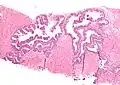

Néoplasie prostatique intraéphithéliale